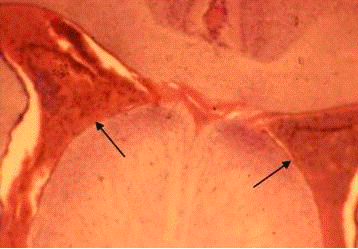

Сопоставление внешних (неврологических и двигательных) эффектов повреждения с результатами морфологического контроля свидетельствуют об определенном соответствии между локализацией и степенью электролитического разрушения мозга, а также характером послеоперационных нарушений.

Так, морфологические исследования не выявили точного попадания коагулирующего электрода в левое вестибулярное ядро Дейтерса в первой группе ни у одной крысы. У животных подгруппы Б, с быстро регрессировавшими послеоперационными неврологическими нарушениями, в двух случаях очаг повреждения захватывал область моторного ядра лицевого нерва и гигантоклеточного ретикулярного ядра; еще в одном наблюдении этот очаг не был обнаружен вовсе. В подгруппе А, у крыс, с отсутствовавшими после операции видимыми изменениям позы и двигательной активности, в 5 случаях имело место попадание коагулирующего электрода в область вентрального и дорсального кохлеарного ядер (рис. 3.5,Б,2), в одном - в левую ножку мозжечка. У одной крысы очаг разрушения не определялся.

Во второй, «осложненной», группе у 8 из 9 крыс обнаружено точное попадание коагулирующего электрода в левое вестибулярное ядро Дейтерса. У одной крысы морфоконтроль не проводился. При этом объем и характер разрушения варьировал у разных животных. Отмечены случаи локального (рис. 3.5,Б,1) и довольно обширного разрушения вестибулярного ядра с большой протяженностью в рострокаудальном направлении (рис. 3.5,Б,3). У двух животных наблюдалось полное замещение области разрушения глиальным рубцом. Важным представляется тот факт, что течение послеоперационного периода по неврологическим показателям не зависело только от объема стволового разрушения. Так, у животного с самым обширным повреждением ядра Дейтерса (рис. 3.5,Б,3) обнаружена достаточно быстрая (через полторы недели) и полная компенсация нарушенных функций. Такими же были сроки редукции неврологических отклонений и в ряде наблюдений с ограниченными разрушениями. В то же время у некоторых крыс с аналогичным или даже меньшим объемом повреждения (рис. 3.5,Б,1) отмечались грубые, не компенсируемые в течение полутора месяцев, поведенческие нарушения. Судя по всему, последствия локального стволового повреждения определяются многими факторами, к числу которых относятся реакция ткани и сосудов мозга на электротравму, целостные церебральные реакции на повреждение и др.

Из семи крыс, погибших во время или в разные сроки после операции, патоморфологические исследования удалось провести лишь в двух случаях. Если в одном из них имело место довольно грубое повреждение ядра Дейтерса, то во втором точное локальное попадание коагулирующего электрода в левое ядро Дейтерса сопровождалось сравнительно небольшим объемом разрушения (рис.3.5,Б,2).

Сходство особенностей гистологической картины повреждения у этого животного и животных из второй группы является еще одним подтверждением нашего вывода о том, что тяжесть послеоперационного состояния не сводится только к локализации и объему разрушения, но определяется, по-видимому, вторичными дисгемическими нарушениями и особенностями протекания системных адаптивно-компенсаторных процессов, которые обусловлены, в частности, индивидуальными особенностями ЦНС.

Рис.3.5. Фронтальные срезы мозга крыс при стволовом повреждении: 1 -вариант с локальным разрушением ВЯД; 2 - повреждение ствола с деструкцией кохлеарных ядер; 3 - обширное разрушение ствола на этом же уровне (показано стрелками)